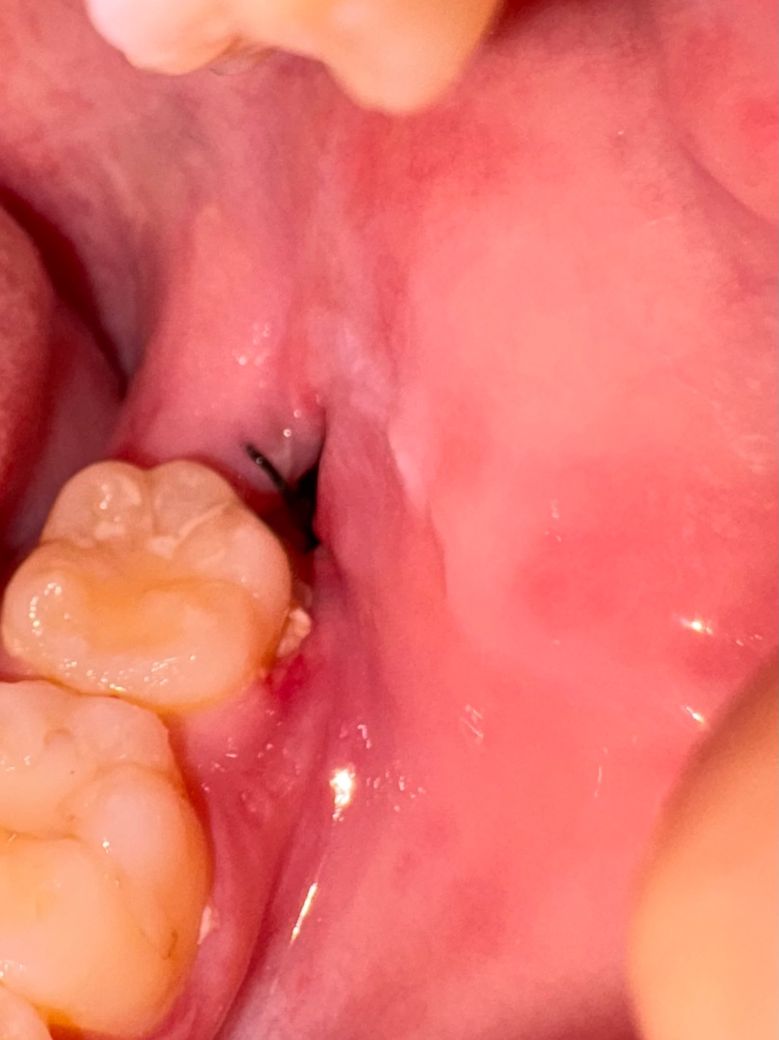

매복 사랑니 발치 부위 하얀 찌꺼기 생김

사진처럼 이빨 뽑은 언쪽이랑 그 앞에 이빨쪽에 하얀 찌꺼기 같은게 생겼어요. 가끔 입에 돌아다녀서 뱉기도 하는데 원래 이런건가요? 아프진 않은데 염증인가요?

뽑은지 일주일 정도 됐는데 잇몸도 부어있어요. 이것고 괜찮은건가요 ㅠ?

• 1번 째 사진

염증은 아니고 사랑니발치한곳 잇몸이 아물면서 생기는 자연스러운 현상이니 크게 걱정하지 않으셔도 될것같습니다.

사진상 보여지는 잇몸 붓기 정도는 발치 후 정상 범주로 보여집니다.

하얀찌꺼기는 이물질 같으니 그냥 뱉으시고, 위생관리 잘해주시기 바랍니다.